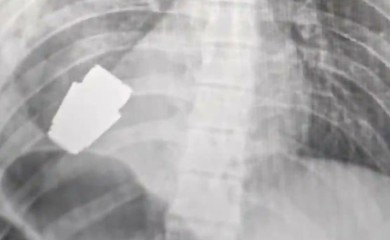

Hirurzi iz grudi ukrajinskog vojnika uklonili neeksplodiranu granatu

Hirurzi su uspješno odstranili oružje koje se nalazilo tik ispod srca vojnika, a u operacionoj sali tokom čitavog zahvata bila su dva stručnjaka za demontiranje eksploziv...